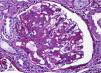

Ante la persistencia de la hematuria macroscópica, se realiza biopsia renal: nefropatía mesangial por IgA, con hallazgos en la microscopia óptica (fig. 2).